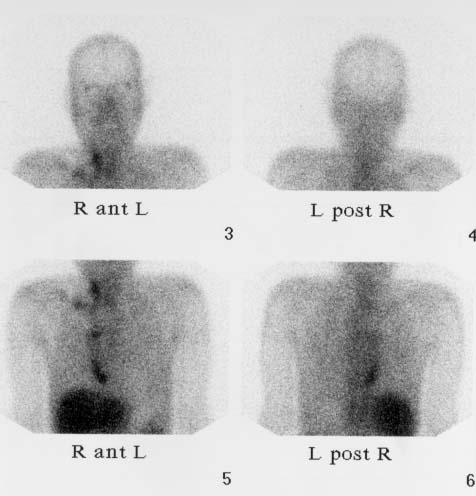

CaseFR01

- Age/Sex: 47F

- Chief Complaint: 後腹膜腫瘍の全身検索

- Clinical

Course: 約10ヶ月間心窩部痛を繰り返し,腹部CTで左後腹膜腫瘤が指摘された.手術で平滑筋肉腫の診断を得たが,骨シンチグラフィ異常を認めた.

- Lab. Data: BUN 8.1,Cr 0.61,Ca 8.1,Pi 2.8,CEA 正常,CA19-9

正常

- Images:

- X-CT, abdomen

- Bone scintigrams, Ant,

Lat

- Skull X-ray, XCT